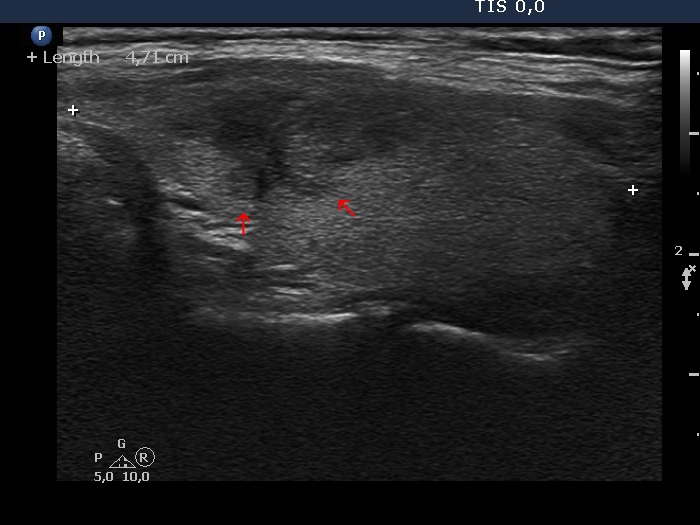

Papillary carcinoma (histology) - case conp003

Transverse scan

Longitudinal scan

Three types of indistinct borders are presented in these images. Green arrows point to that part of the nodule which echogenicity is identical to the extrathyroidal strap muscle. The tumor has partly blurred (red arrows) and partly spiculated (yellow arrows) margins.